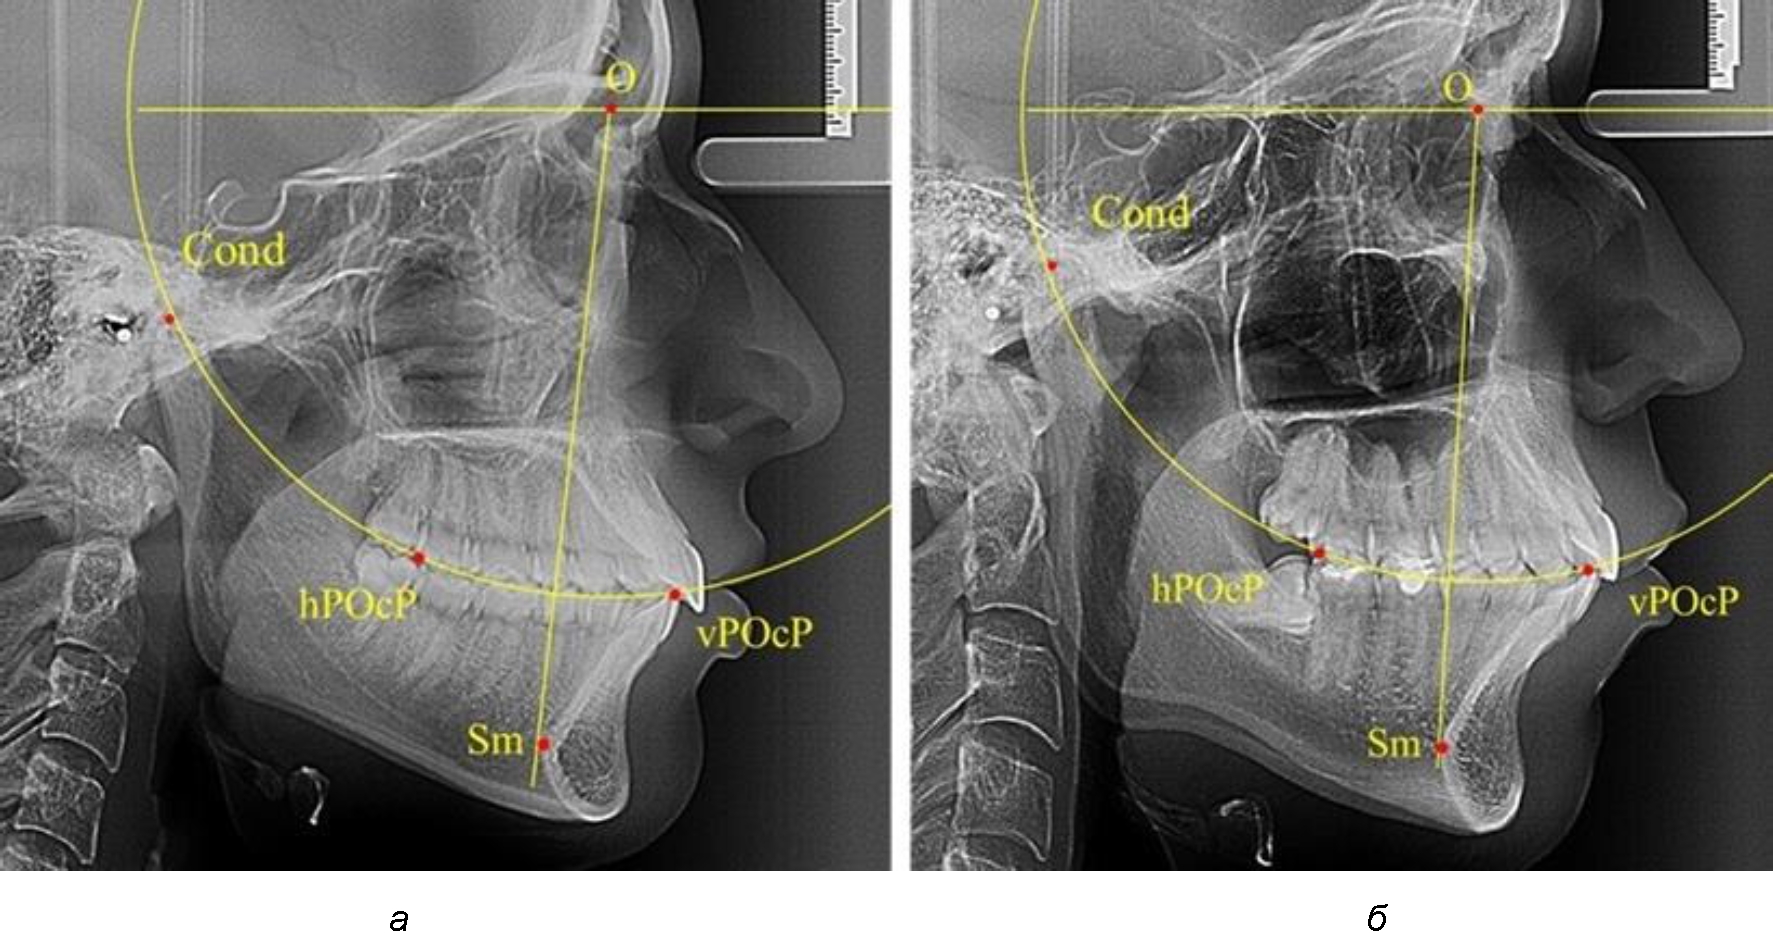

В группе рентгенограмм с ретрузионным положением резцов также проводилось распределение на подгруппы с учетом широтных размеров подбородочного выступа.

Анализ результатов показал, что практически при всех вариантах подбородочного выступа в данной группе исследования первые премоляры, как правило, располагались либо на стресс-оси Bimler, либо позади. Рентгенограммы пациентов с ретрузионным положением резцов при широком и среднем варианте подбородочного выступа представлены на рис. 4.

Таким образом, для людей с ретрузионным типом зубочелюстных дуг характерно расположение первых премоляров позади стресс-оси либо на средней линии, и этот показатель не может быть использован в качестве выбора метода лечения аномалий для данной группы исследования вне зависимости от формы подбородочного выступа.

Рис. 4. Положение первых верхних премоляров при ретрузии с широкими (а) и средними (б) размерами подбородка

Результаты проведенного исследования показали зависимость расположения первых премоляров от положения передних зубов и вариабельности расположения межрезцовой точки. Отмечено, что при протрузионном положении резцов у людей с физиологическим прикусом смещение первых премоляров кпереди от стресс-оси Bimler не может быть показанием к удалению первых премоляров при патологической окклюзии с однотипными зубными дугами. В то же время расположение первых верхних премоляров позади или на линии Bimler у людей с ретрузинным типом дуг также не является противопоказанием к экстракционным методам лечения.

Ширина подбородочного выступа также оказывает влияние на положение стресс-оси Bimler.